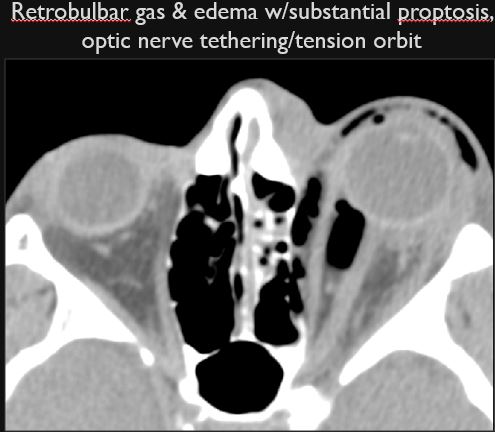

Proptosis or enophthalmos is present. [Yes/No]

The optic sheath/nerve has a stretched appearance. [Yes/No]

The posterior aspect of the globe is tented in appearance. [Yes/No]

Signs of tension orbit are present. [Yes/No]

There is an abnormal air collection in the postseptal extraconal or intraconal orbital compartments likely due to a blunt or penetrating injury. [Yes/No]